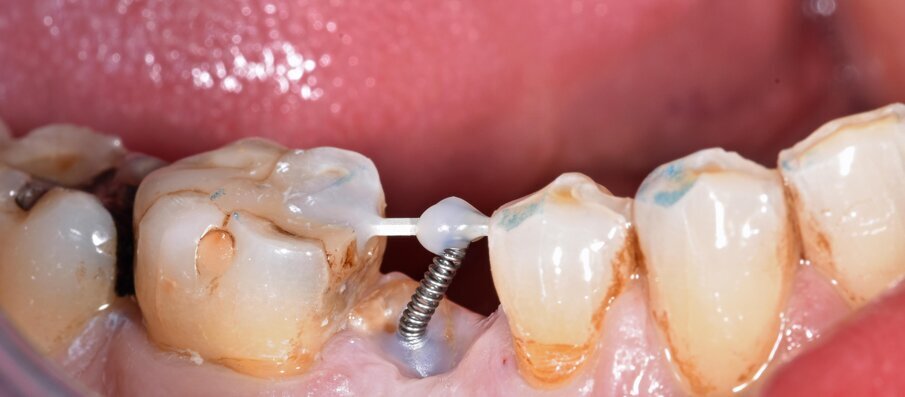

Per ottenere questo risultato nel gennaio 2021 è stato ancorato un segmento di arco in acciaio a sezione quadrata 0.021” x 0.025” agli elementi 4.4 e 4.6 per mezzo di composito. Il segmento è servito da ancoraggio per una molla con forza di trazione 150 g in posizione obliqua in senso disto-mesiale.

L’estrusione completa del frammento ha richiesto un tempo di 6 mesi, durante i quali è stata modificata più volte l’inclinazione della molla per evitare che il movimento diventasse ortogonale al segmento e mantenere la traiettoria prevista. Così facendo, è stato possibile rigenerare naturalmente l’intero alveolo e inserire, dopo 3 mesi di ulteriore maturazione del tessuto, in un contesto osseo ideale e perfettamente rigenerato un impianto Syra (Sweden & Martina) di diametro 4.25 mm e lungo 11 mm.